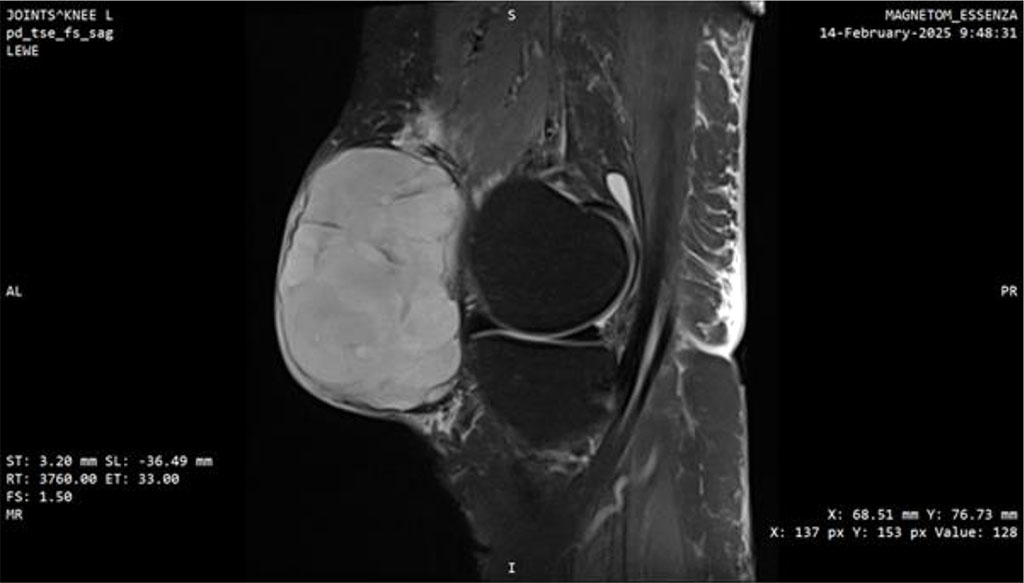

At this point, the patient was transferred to a center of the highest reference, specializing in sarcomas. MRI performed there demonstrated a well-defined, heterogeneously enhancing solid mass measuring 77 × 45 × 78 mm with surrounding fat stranding. A repeat biopsy was performed, and the third histopathological result confirmed myxofibrosarcoma, FNCLCC grade 3 (Fig. 3, 4).

Figure 3: MRI scan of the knee joint with Myxofibrosarcoma (MFS). Sagittal plane.